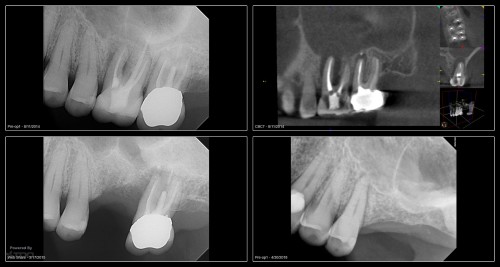

Another 6-Month Follow-up

From last week. 59yof. SIP. Hyperemic. 6 canals. 2 visits. Asymptomatic at the second visit. […]